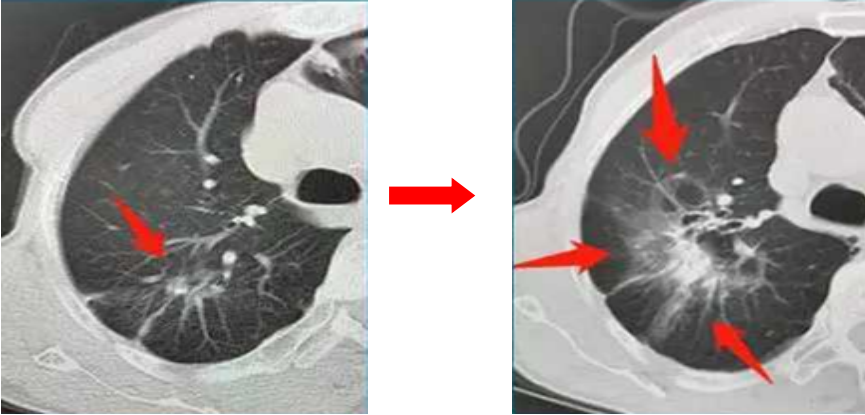

55歲的張先生兩年前查體發(fā)現(xiàn)了肺結(jié)節(jié),認為自己既不抽煙,也不熬夜、酗酒,更沒有什么癥狀,應該沒什么事。醫(yī)生建議他每3個月復查一次CT,他置之不理,認為自己好端端的,干嘛還浪費那錢。結(jié)果兩年后出現(xiàn)咳嗽胸痛才想起來就診,發(fā)現(xiàn)原來5mm的肺結(jié)節(jié)已經(jīng)長大了(見下圖),還出現(xiàn)了轉(zhuǎn)移,診斷為晚期肺癌,悔之晚矣。

1.結(jié)節(jié)的形態(tài)變化:肺結(jié)節(jié)持續(xù)存在且逐漸增大、密度逐漸增高,惡變可能性大,短期內(nèi)結(jié)節(jié)大小急劇變化的多為良性。若結(jié)節(jié)8mm~15mm,有分葉、毛刺、胸膜牽拉、含氣細支氣管征和小泡征、偏心厚壁空洞這些CT惡性征象,大概率是惡性的。